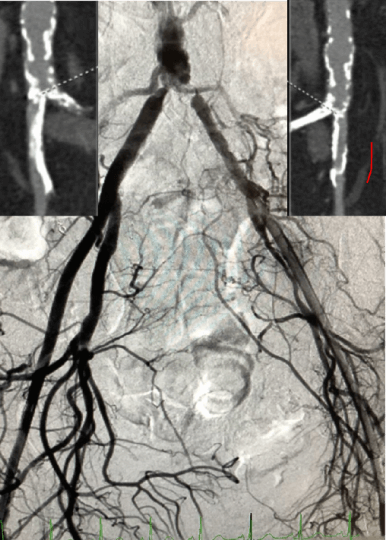

Case courtesy of Dr. Samer Garas

European Registry: IVL to facilitate transfemoral TAVR

Shockwave IVL has helped expand the indications for TF TAVR in patients with severe calcific peripheral artery disease (PAD).